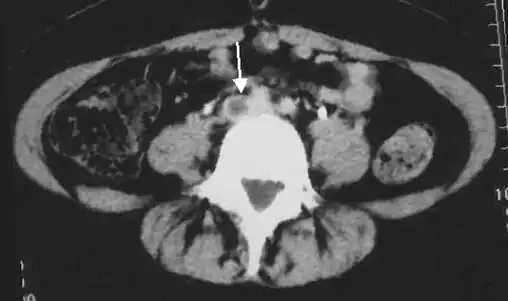

A pulmonary embolism (PE) occurs when a blood clot from a deep vein (a DVT) detaches from a vein (embolizes), travels through the right side of the heart, and becomes lodged as an embolus in a pulmonary artery that supplies deoxygenated blood to the lungs for oxygenation.[28] Up to one-fourth of PE cases are thought to result in sudden death.[12] When not fatal, PE can cause symptoms such as sudden onset shortness of breath or chest pain, coughing up blood (hemoptysis), and fainting (syncope).[29][30] The chest pain can be pleuritic (worsened by deep breaths)[29] and can vary based upon where the embolus is lodged in the lungs. An estimated 30–50% of those with PE have detectable DVT by compression ultrasound.[30]

Thrombolysis is the injection of an enzyme into the veins to dissolve blood clots, and while this treatment has been proven effective against the life-threatening emergency clots of stroke and heart attacks, randomized controlled trials[139][140][141] have not established a net benefit in those with acute proximal DVT.[5][142] Drawbacks of catheter-directed thrombolysis (the preferred method of administering the clot-busting enzyme[5]) include a risk of bleeding, complexity,[l] and the cost of the procedure.[125] Although, while anticoagulation is the preferred treatment for DVT,[125] thrombolysis is a treatment option for those with the severe DVT form of phlegmasia cerula dorens (bottom left image) and in some younger patients with DVT affecting the iliac and common femoral veins.[12] Of note, a variety of contraindications to thrombolysis exist.[125] In 2020, NICE kept their 2012 recommendations that catheter-directed thrombolysis should be considered in those with iliofemoral DVT who have "symptoms lasting less than 14 days, good functional status, a life expectancy of 1 year or more, and a low risk of bleeding."[138]

A mechanical thrombectomy device can remove DVT clots, particularly in acute iliofemoral DVT (DVT of the major veins in the pelvis), but there is limited data on its efficacy. It is usually combined with thrombolysis, and sometimes, temporary IVC filters are placed to protect against PE during the procedure.[143] Catheter-directed thrombolysis with thrombectomy[141] against iliofemoral DVT has been associated with a reduction in the severity of post-thrombotic syndrome at an estimated cost-effectiveness ratio of about $138,000[m] per gained QALY.[144][145] Phlegmasia cerulea dolens might be treated with catheter-directed thrombolysis and/or thrombectomy.[19][143]